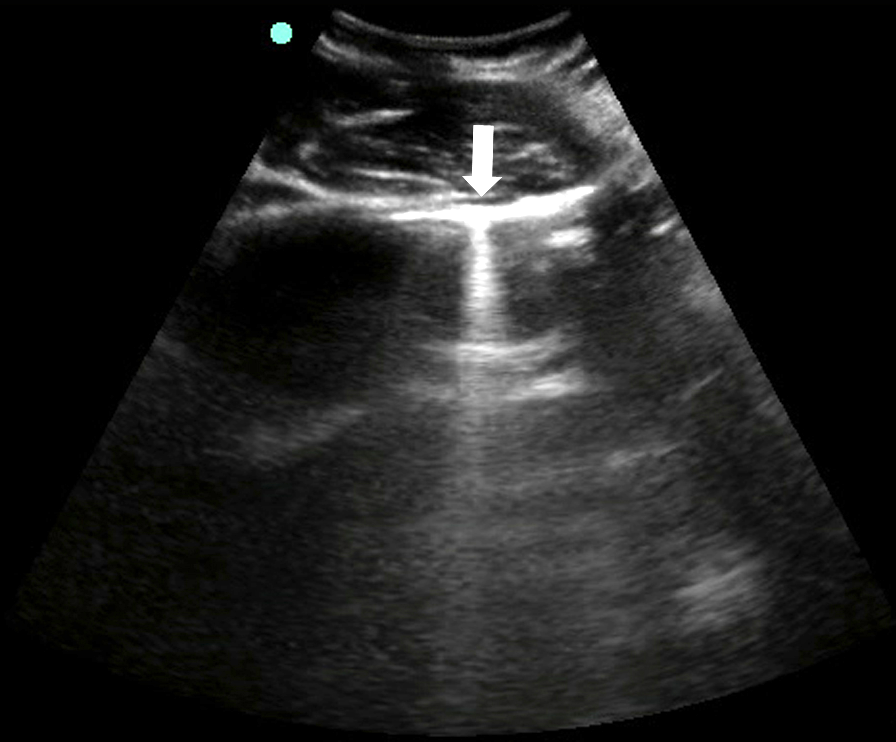

- Figure 18. Pleural effusion with spine sign

- Quad sign delineates four boundaries: superior and inferior rib shadows, superficial parietal pleura, and the deeper visceral pleura.

- Mirror image artifact60

- Sound waves reflect off the highly reflective diaphragm, encounter liver tissue, are reflected back to the diaphragm, and then return to the transducer. Based on the time taken for the sound waves to return to the transducer, the machine incorrectly assumes that the initial beam traveled along a linear path and reached the liver tissue deep to the diaphragm. The liver is thus mapped falsely in the deeper location.